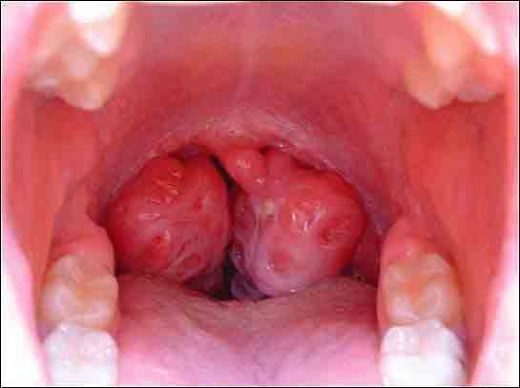

Sol Bademcik Şişmesi: Belirtileri ve Tedavisi

Sol bademcik şişmesi, genellikle boğazın arka kısmında yer alan lenfoid dokunun iltihaplanması veya enfekte olması durumudur. Bademcikler, bağışıklık sisteminin bir parçası olarak, vücut savunmasında önemli bir rol oynamaktadır. Bu durum, çeşitli etkenlerden kaynaklanabilir ve genellikle enfeksiyon belirtisi olarak ortaya çıkar.